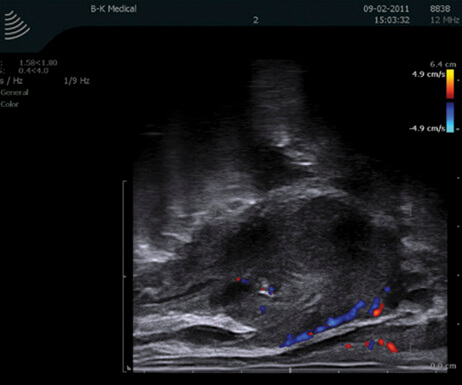

Στους κακοήθεις όγκους του νεφρού, ειδικά στους μικρούς όγκους όπου υπάρχει ένδειξη για ρομποτική μερική νεφρεκτομή, η εφαρμογή των ρομποτικών υπερήχων προσφέρει πολύτιμη βοήθεια. Η ρομποτική μερική νεφρεκτομή, ακόμα και όταν εκτελείται από έμπειρο ρομποτικό χειρουργό, αποτελεί μια δύσκολη τεχνικά επέμβαση. Εδικότερα, μικροί όγκοι που εντοπίζονται κοντά στα αγγεία ή που βρίσκονται «κρυμμένοι» μέσα στο νεφρό χωρίς να εξέχουν από την επιφάνειά του, έχουν μεγάλο βαθμό δυσκολίας στην εξαίρεσή τους. Εδώ ακριβώς η χρήση του ρομποτικού υπερήχου κάνει τη διαφορά, ενισχύοντας τις δυνατότητες που μας προσφέρει η ρομποτική χειρουργική. Η εφαρμογή του υπερήχου εξαλείφει το μειονέκτημα της έλλειψης της αφής των δομών εντός του σώματος, αναγνωρίζει με ακρίβεια την εντόπιση του όγκου αλλά και τα αγγεία που τον αιματώνουν, αναγνωρίζει τα όρια του όγκου έτσι ώστε η εκτομή του να γίνει επί υγιών ορίων, μειώνοντας έτσι την πιθανότητα υποτροπής. Ο χειρουργός μέσω του υπερήχου «βλέπει» μέσα στο νεφρό και αφαιρεί τον όγκο διατηρώντας ταυτόχρονα το μεγαλύτερο τμήμα του οργάνου.